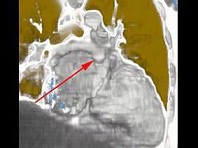

影像检查如图,最可能的诊断是()

• A.正常结构

• B.心房血栓

• C.心脏息肉

• D.心房黏液瘤

• E.以上都不是